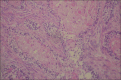

Context: Ameloblastomas are benign tumors of the jaws with locally invasive capacity.

Results: The mean age of the patients at presentation was 35.1 ± 16.8 years with a slight female preference. The peak prevalence was in the 11- to 20-year age group and declined with increasing age. Total 75 patients were black and 37 were white, for a 2:1 black: white ratio. The location of the ameloblastomas showed a marked predominance in the mandible (84.8%) and 69% of the cases presented with a multilocular radiographic appearance. The tumor was associated with an embedded tooth in 14 cases (12.7%): nine unilocular and five multilocular ameloblastomas. The maximum radiological extension of the lesions on panoramic radiographs was 0.5-20 cm (mean ± SD: 5.2 ± 3.3 cm) and most cases were symptom-free (75.9%). Solid/multicystic ameloblastoma was the most common clinicopathologic subtype. There was an association between the clinicopathologic subtypes and radiographic appearance (P < 0.001). Recurrence was observed in 13.3% of cases.